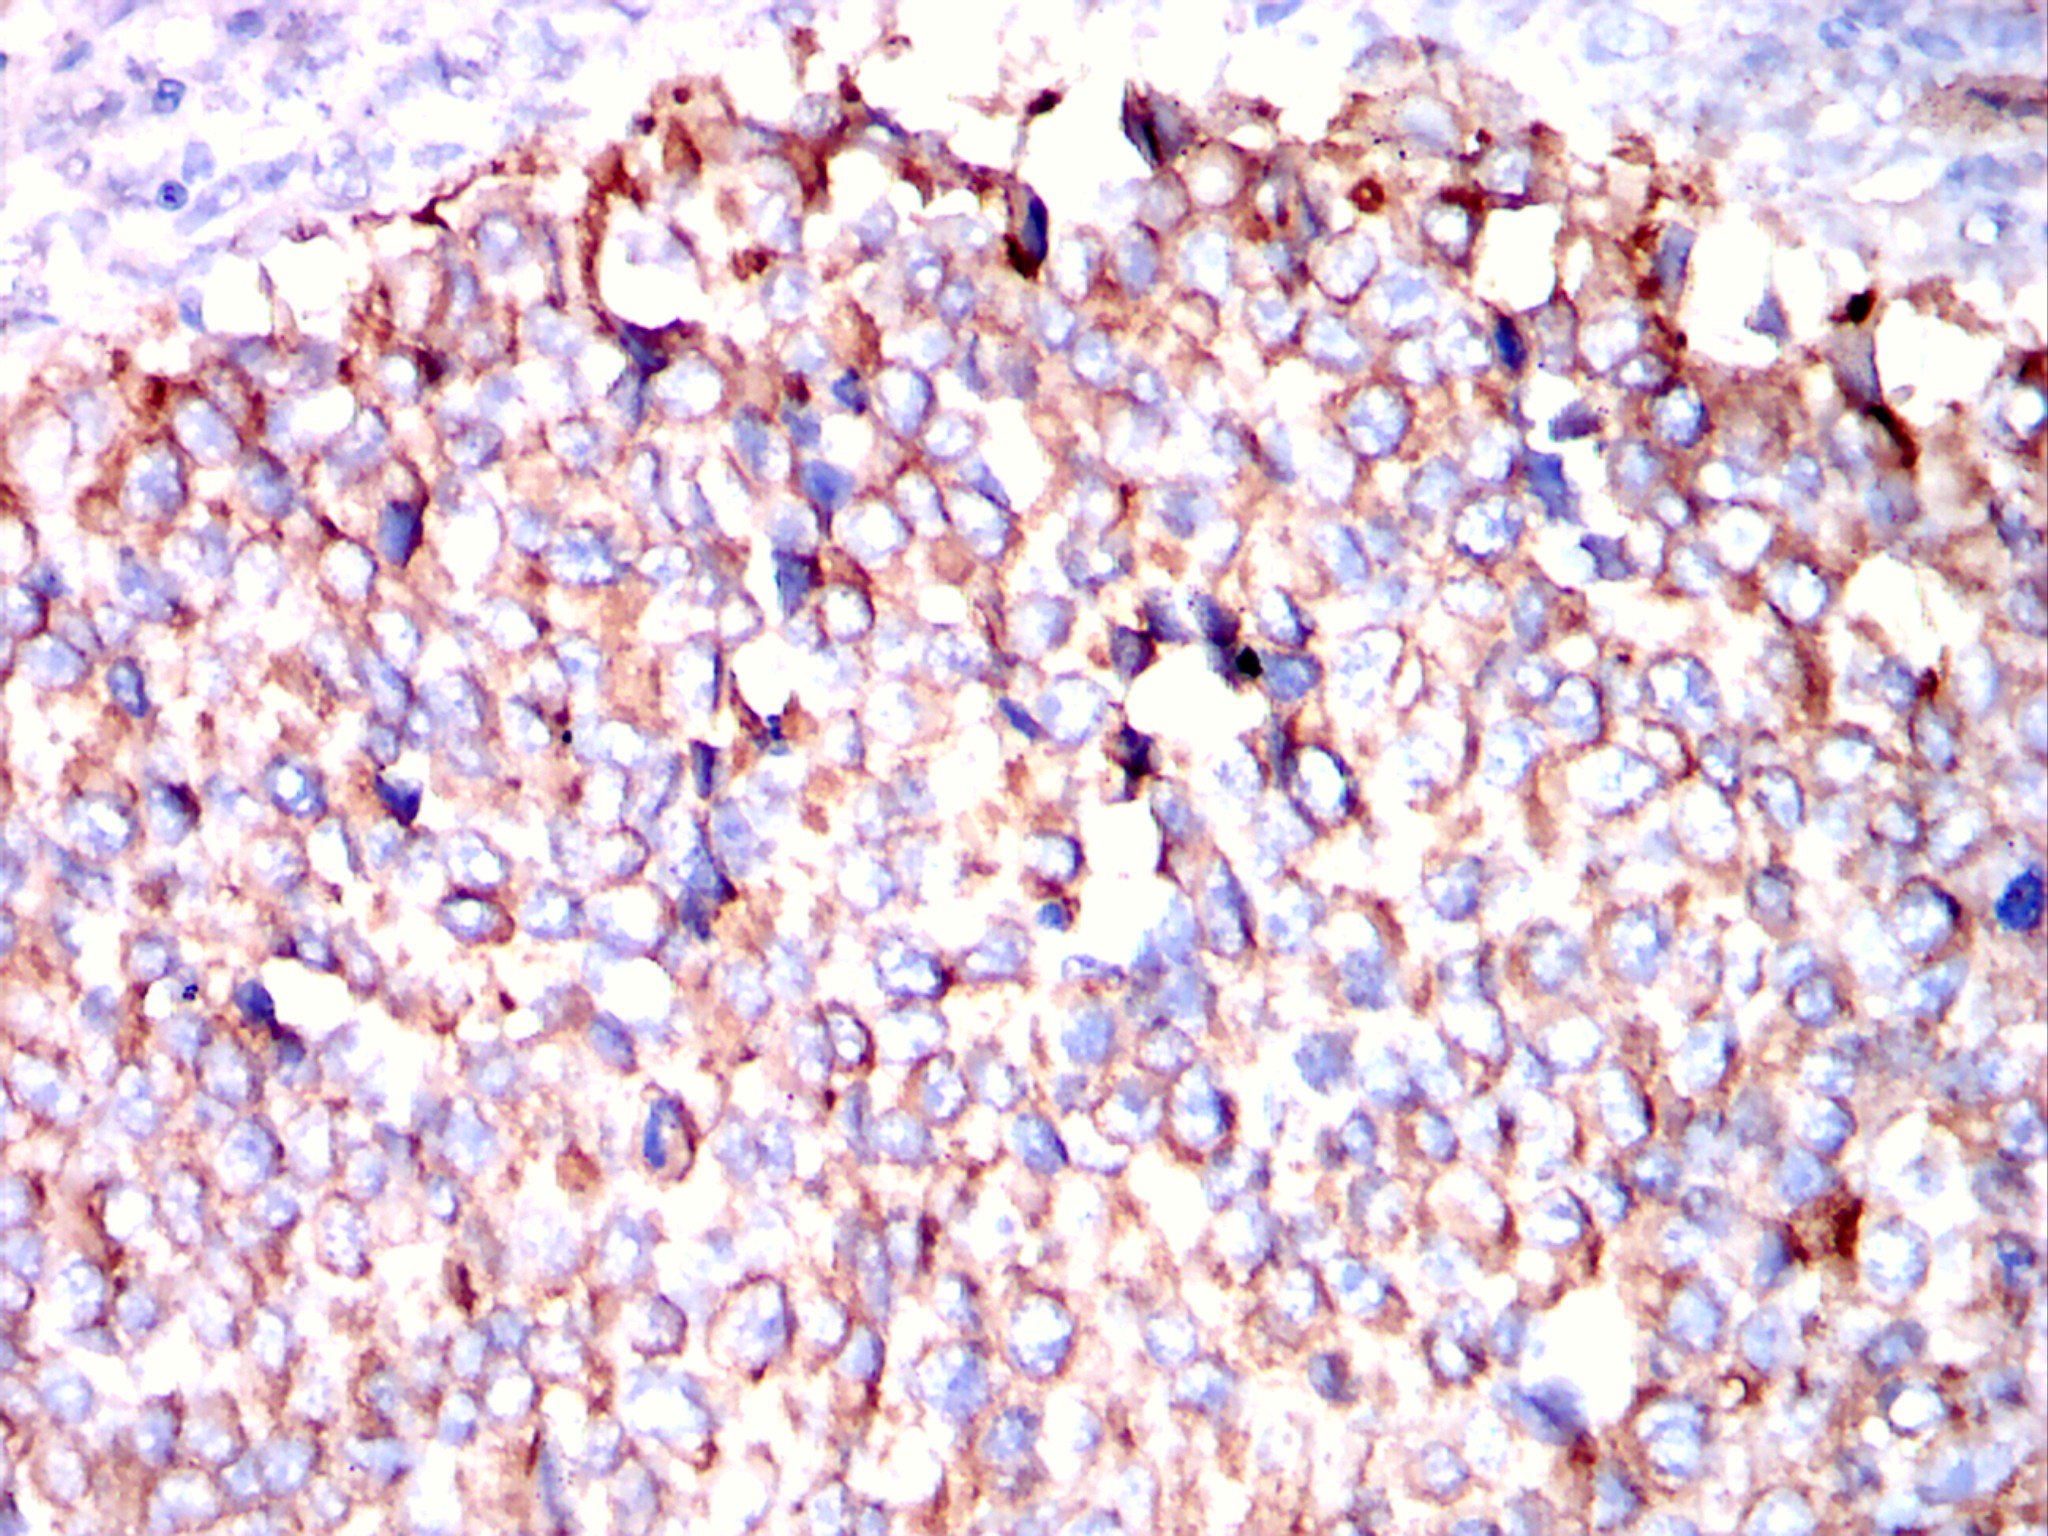

分类: 科研抗体货号: 20297别名: CK19; K1CS; MGC15366; KRT19应用: IHC, IF, FCM反应种属: Human, Mouse, Rabbit